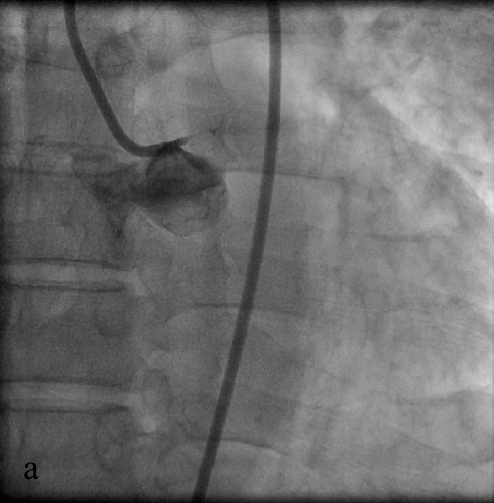

На исходных коронарограммах выявляются тотальная окклюзия ствола ЛКА (а), система ЛКА заполняется по межсистемным коллатералям из бассейна ПКА (б).